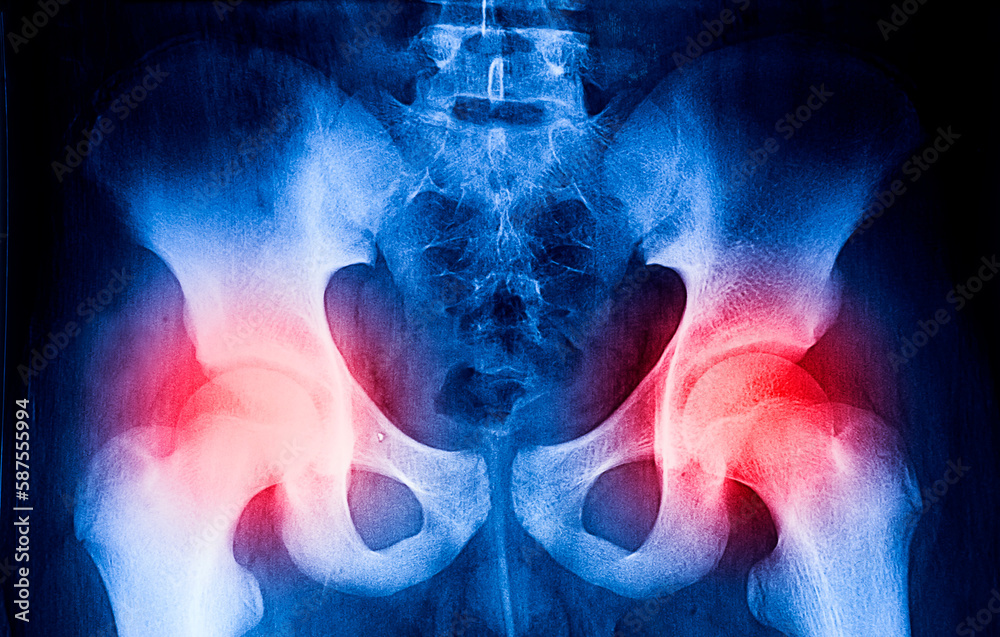

From www.shutterstock.com

Film Xray Pelvis Arthritis Both Hip Stock Photo 204262261 Shutterstock Arthritis In Hip And Pelvis hip osteoarthritis (degenerative arthritis of the hip) medically reviewed by david zelman, md on june 02, 2024. What are the symptoms and treatments for hip arthritis? Hip arthritis is pain and stiffness in your hip joint, related to the soft tissues in the joint. what is hip arthritis? arthritis is a common cause of pain, inflammation, and. Arthritis In Hip And Pelvis.